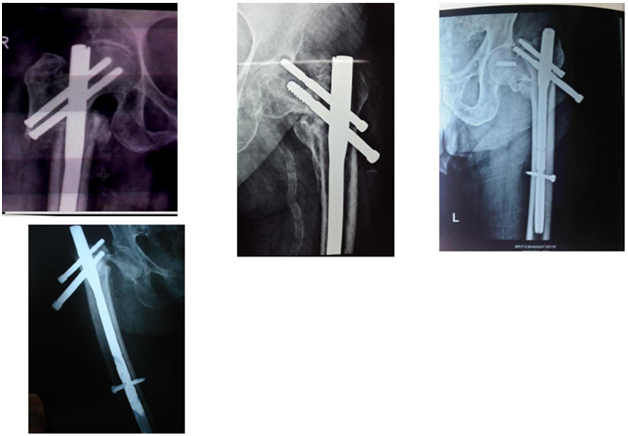

4. Often has 2 Screws in head.  Lag screw and hip pin.  Controls rotation well (Figures 2 & 3).

Figure 2 PFN Biomechanically stronger than DHS.

Figure 3 Excessive collapse with DHS within first week. ?Due to lateral wall comminution.